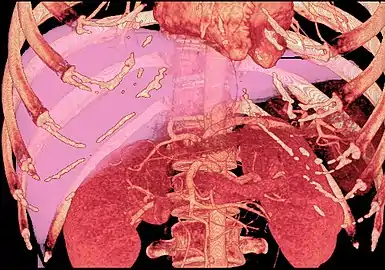

With the recent advances of noninvasive imaging, living liver donors usually have to undergo imaging examinations for liver anatomy to decide if the anatomy is feasible for donation. The evaluation is usually performed by multidetector row computed tomography (MDCT) and magnetic resonance imaging (MRI). MDCT is good in vascular anatomy and volumetry. MRI is used for biliary tree anatomy. Donors with very unusual vascular anatomy, which makes them unsuitable for donation, could be screened out to avoid unnecessary operations.

MDCT image. Arterial anatomy contraindicated for liver donation

MDCT image. Portal venous anatomy contraindicated for liver donation

MDCT image. 3D image created by MDCT can clearly visualize the liver, measure the liver volume, and plan the dissection plane to facilitate the liver transplantation procedure.

Phase contrast CT image. Contrast is perfusing the right liver but not the left due to a left portal vein thrombus.